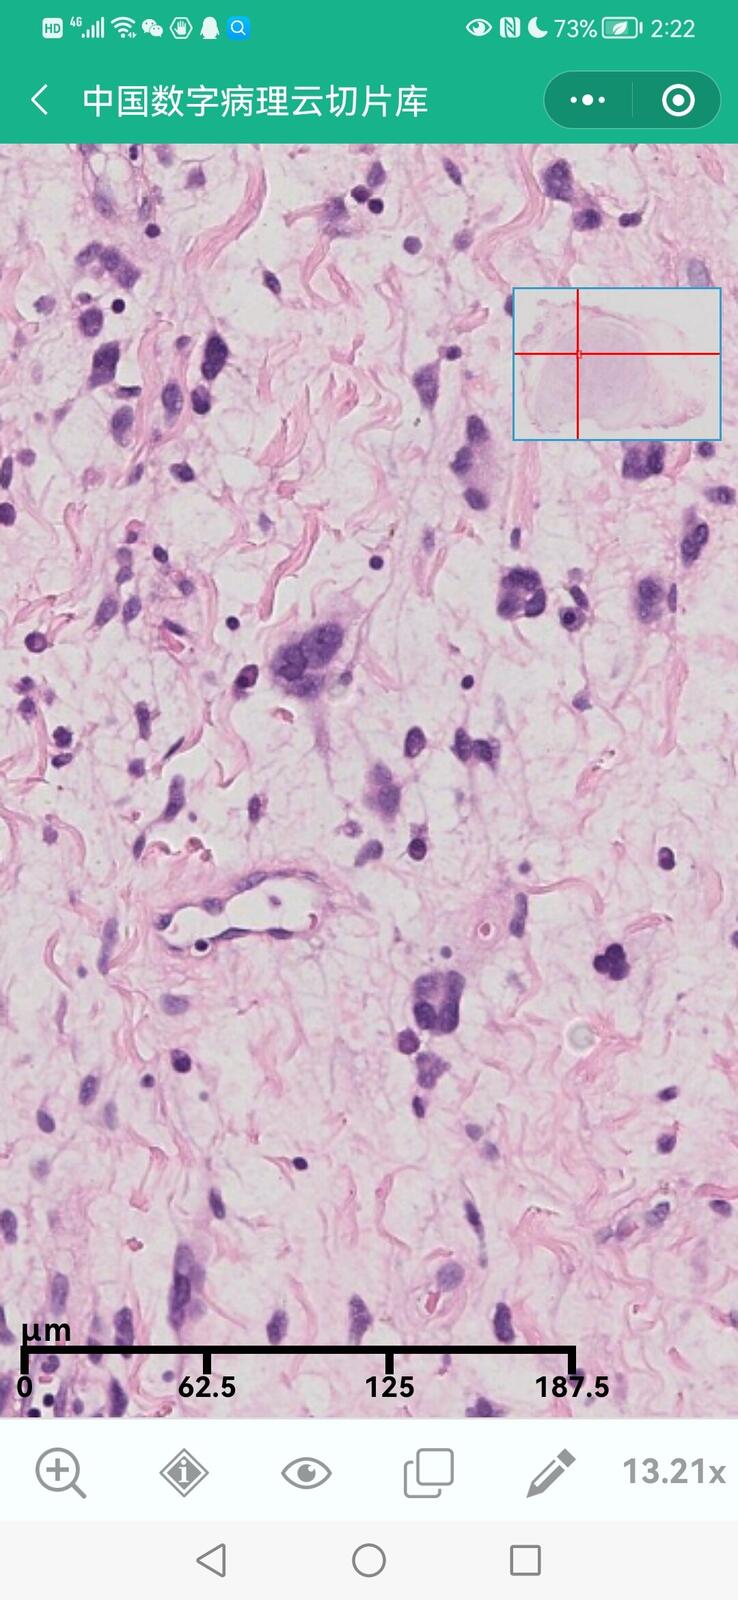

乳腺分泌性癌(29岁)